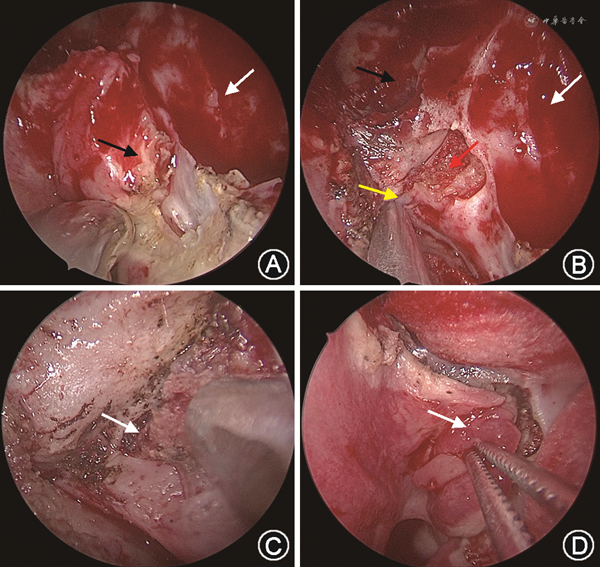

内镜下经中鼻道VN是目前较为主要的入路方式:术者经内镜在中鼻甲后端附着缘上方由内上至外下做一弧形切口,切口边缘达后鼻孔上方;向腭骨垂直板与蝶骨交界处分离黏膜瓣,去除腭骨蝶突,暴露腭鞘管并切断腭鞘管神经血管束;分离寻找前后开口的翼管,在翼管前口切断翼管神经并电凝断端(图2)。该术式于鼻内镜技术发展后采用较多,其特点为操作简便、视野清晰、创伤小、鼻腔并发症发生率低,既往多用于治疗顽固性VMR。但由于切断翼管神经主干时未对其分支进一步分离,故患者鼻分泌物减少的同时会出现眼鼻干燥、上唇和腭部麻木等分支切断并发症。如术中翼管暴露不佳时需进入翼腭窝,还存在损伤其内组织的风险。

翼管神经分支切断术是在经中鼻道VN的基础上,充分显露蝶腭动脉及腭骨筛嵴,沿蝶腭孔周围环形切开黏骨膜,同时切断鼻后神经丛上鼻甲支、鼻中隔支和鼻腔外侧壁支的血管神经束,在腭鞘管前口内侧骨管内切断咽支及与其伴行的蝶腭动脉咽支。因选择性切断鼻后神经丛而并非翼管神经,可减少眼干、上腭麻木等并发症[30, 31];因不进入翼腭窝,翼管区周围组织损伤小,可降低术中、术后出血风险,提高患者生活质量[31]。